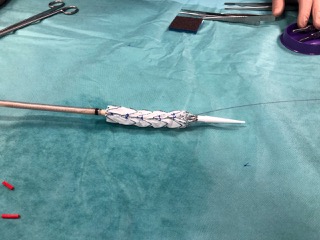

Nasi chirurdzy naczyniowi z Aortic Team znów pierwsi w kraju!

2022-11-07Lekarze Kliniki Chirurgii Naczyniowej, Ogólnej i Angiologii naszego szpitala dokonali pierwszego w kraju, całkowicie przezskórnego wszczepienia modyfikowanego stent-graftu. Była to operacja ratująca życie, a pomocna przy tym - technika druku 3D.

Dostępy całkowicie przezskórne (bez cięcia skóry) wykonuje tylko kilka ośrodków w Polsce i jest to metoda coraz częściej preferowana, ale głównie do mniej skomplikowanych przypadków. Tym razem do szpitala na Pomorzanach trafił 75-letni pacjent z objawowym tętniakiem okołotrzewnym (aorty piersiowo-brzusznej) - bolesnym, grożącym pęknięciem, a zatem stanowiącym zagrożenie życia. Dodatkowo chory nie miał szans na skorzystanie ze standardowego stent-graftu branchowego (z doszywanymi „rękawkami” na naczynia) czy fenestrowanego (z wyciętymi „okienkami” na naczynia) zamawianego u producenta z powodu występujących u niego dodatkowych naczyń, odchodzących od aorty (osobne ujście tętnicy wątrobowej). Nie mógł też czekać na wyprodukowanie stent-graftu szytego dla niego na miarę, bo trwałoby to 8-12 tygodni, a bolesność tętnika świadczyła, że rychło pęknie. Groziło to śmiercią pacjenta.

Leczenie stent-graftami modyfikowanymi jest w domeną naszych lekarzy Kliniki Chirurgii Naczyniowej, Ogólnej i Angiologii, którzy wypracowali wysokiej jakości standard postępowania w użyciu tej metody. Wykorzystując model aorty danego pacjenta, wydrukowany techniką 3D, modyfikują własnoręcznie, już na sali operacyjnej standardowe stent-grafty i dopasowują je indywidualnie do anatomii operowanego pacjenta. Po co? Bo mimo ogólnej takiej samej budowy każdego z nas, układ naczyń krwionośnych, ich budowa, odległości między poszczególnymi naczyniami różnią się u każdego człowieka. Dlatego dla efektywności działania wszczepianego, standardowego stent-graftu – proteza ta powinna być dopasowana do budowy chorego. Chirurdzy naczyniowi USK-2 są jedynym zespołem w Polsce, który tego typu zabiegi wykonuje rutynowo, również w przypadkach nagłych. Jednak taki sposób leczenia, jak i wszelkie inne zaawansowane procedury aortalne, wymaga licznych, często trudnych dostępów naczyniowych (np. nacięć w pachwinach, rękach i klatce piersiowej) – tj. cięć i operowania „na otwarto”. Dla chirurga taka operacja jest łatwiejsza, bo pole operacyjne jest widoczne jak na dłoni. Ale dla pacjenta dochodzenia do formy po takiej operacji jest długotrwałe, bolesne i mało komfortowe. Dlatego użycie przez szczecińskich lekarzy wyłącznie dostępu przezskórnego (bez cięcia) w leczeniu tętnika jest dużym krokiem na przód w chirurgii naczyniowej, a fakt, że to pierwszy tego typu zabieg w Polsce to ogromny sukces naszych „naczyniowców” i świadczy o ich doskonałej technice operowania.

„Modyfikacja stent-grafu naszą, ‘szczecińską metodą’ pozwoliła na pokonanie technicznych trudności, dostosowanie protezy do chorego i wykonanie zabiegu „od ręki”. Zastosowaliśmy modyfikację stent-graftu z okienkami na cztery naczynia trzewne - mówi dr hab. n. med. Arkadiusz Kazimierczak, który wraz z dr. n. med. Pawłem Rynio operował mężczyznę. „Wykonanie przezskórne - dwa dostępy do tętnicy podobojczykowej na klatce piersiowej i obu udowych w pachwinach, zamiast jak dotychczas czterech - pozwoliło na zminimalizowanie urazu operacyjnego tak, że chory był w pełni uruchomiony już w pierwszej dobie po zabiegu i zapytał o termin wypisu ze szpitala – dodaje dr Paweł Rynio. Operacja odbyła się 20 września.

Obaj lekarze są członkami szczecińskiego Aortic Teamu, zespołu chirurgów naczyniowych i kardiochirurgów stosujących nowatorskie metody leczenia w przypadku tętniaków. Zespół planuje rozszerzenie wskazań do zabiegów całkowicie przezskórnych w leczeniu patologii łuku aorty. Pierwsze próby z ograniczeniem urazu operacyjnego w tym zakresie zostały już podjęte w przypadku innej operowanej chorej. Tym razem zastosowano dwa małe cięcia przy wymianie całego łuku aorty, zamiast jak dotychczas pięciu. Pacjentka również jest w dobrym stanie.

Tłumacząc obrazowo - tętniakiem aorty nazywany nadmierne (o ponad 50%) poszerzenie aorty, która jest największą tętnicą w ciele człowieka. Może ono występować na każdym jej odcinku, ale najczęściej występuje w części brzusznej. Przyczyną ich powstania jest odkładanie się blaszek miażdżycowych, nadciśnienie tętnicze, nadmierny, gwałtowny wysiłek czy uraz, czasem także wrodzone nieprawidłowości w budowie naczynia. Ryzyko wystąpienie tętniaka aorty brzusznej wzrasta z wiekiem i jest szczególnie wysokie u mężczyzn około 65. roku życia. Szczególnie niebezpieczne są tętniaki bezobjawowe, które w każdej chwili mogą grozić pęknięciem i prowadzić do zgonu chorego.

Fot. USK-2

„Pola operacyjne” pacjenta – niewielki ślad po wkłuciach do tętnicy podobojczykowej